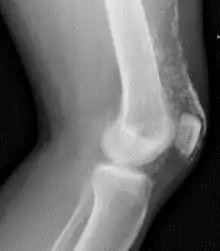

![]() Rayos X de la rodilla de un paciente con dermatomiositis | ||